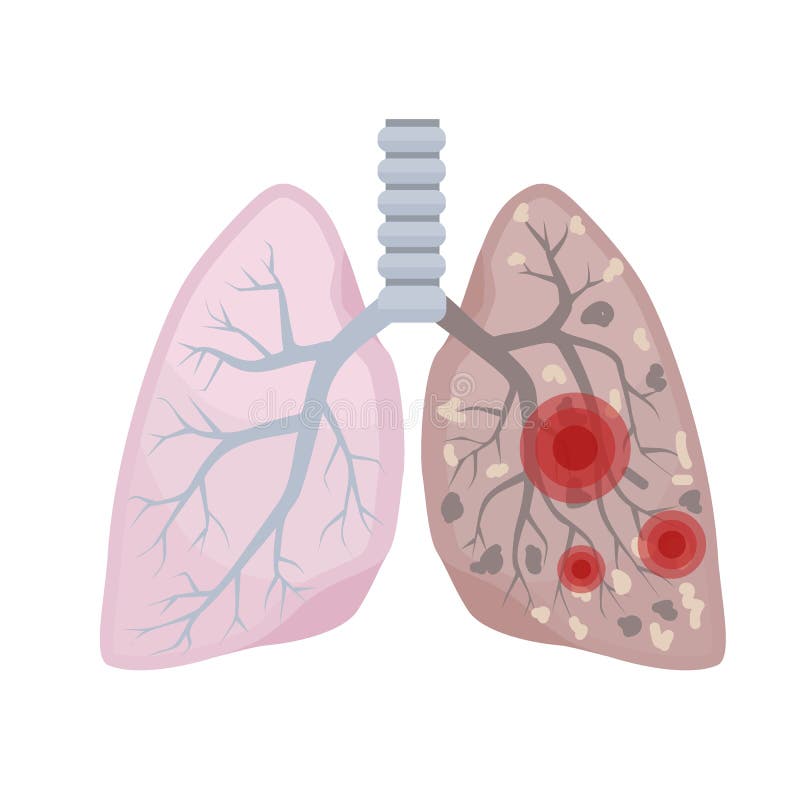

Lista es una colección y muestra de imágenes sobre imagenes de pulmones sanos y enfermos realizada por upup.edu.vn. Además, hay imágenes relacionadas con imagenes de pulmones sanos, imágenes de pulmones sanos, radiografía de pulmones sanos y enfermos, fotos de pulmones sanos, radiografía pulmones sanos y enfermos, rayos x de pulmones sanos y enfermos, pulmon sano y enfermo, pulmón sano y enfermo . Para más información, consulta a continuación.

imagenes de pulmones sanos y enfermos

Posts: imagenes de pulmones sanos y enfermos